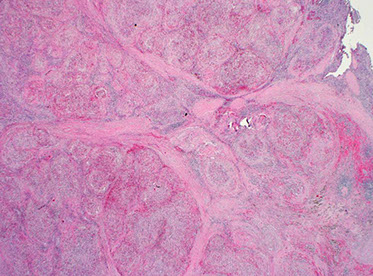

In this case of progressive transformation of germinal centers, there are 3 progressively transformed follicles (solid white arrow) These nodules are 3-4x larger than usual hyperplastic follicles (open white arrows) and are composed of reactive germinal centers infiltrated and disrupted by small lymphocytes.

PTGC, inward expansion of GCs [7]